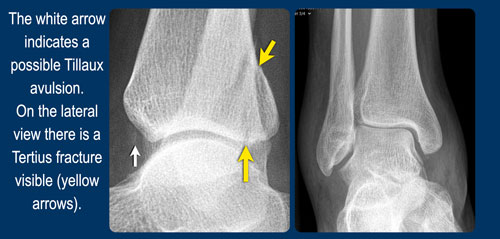

- Đứt khớp chày mác trước (anterior syndesmosis) hoặc ít gặp hơn là gãy kiểu Tillaux (bong điểm bám phía xương chày).

- Gãy bong điểm bám mắt cá sau (tertius avulsion fracture) hoặc đứt khớp chày mác sau (posterior syndesmosis).

Gãy xương Tillaux

Cơ chế chấn thương gây ra gãy xương Weber B có thể dừng lại ở bất kỳ giai đoạn nào. Thường gặp nhất là giai đoạn 2 với đường gãy chéo của xương mác, nhưng đôi khi tổn thương chỉ dừng lại ở giai đoạn 1.

Thông thường đây là tình trạng đứt dây chằng chày mác trước và không thấy bất thường trên phim X-quang, tuy nhiên bệnh nhân sẽ đau nhiều tại vị trí đặc hiệu ở phía trước ngoài. Lực căng tại dây chằng chày mác trước đôi khi có thể gây bong điểm bám của dây chằng này tại xương chày, được gọi là gãy xương Tillaux. Bong điểm bám tại xương mác còn hiếm gặp hơn.

Hình ảnh

Trên tư thế chụp thẳng (AP) và tái tạo CT mặt phẳng coronal, chúng ta thấy gãy xương Tillaux ở giai đoạn 1. Không ghi nhận tổn thương gãy xương nào khác.